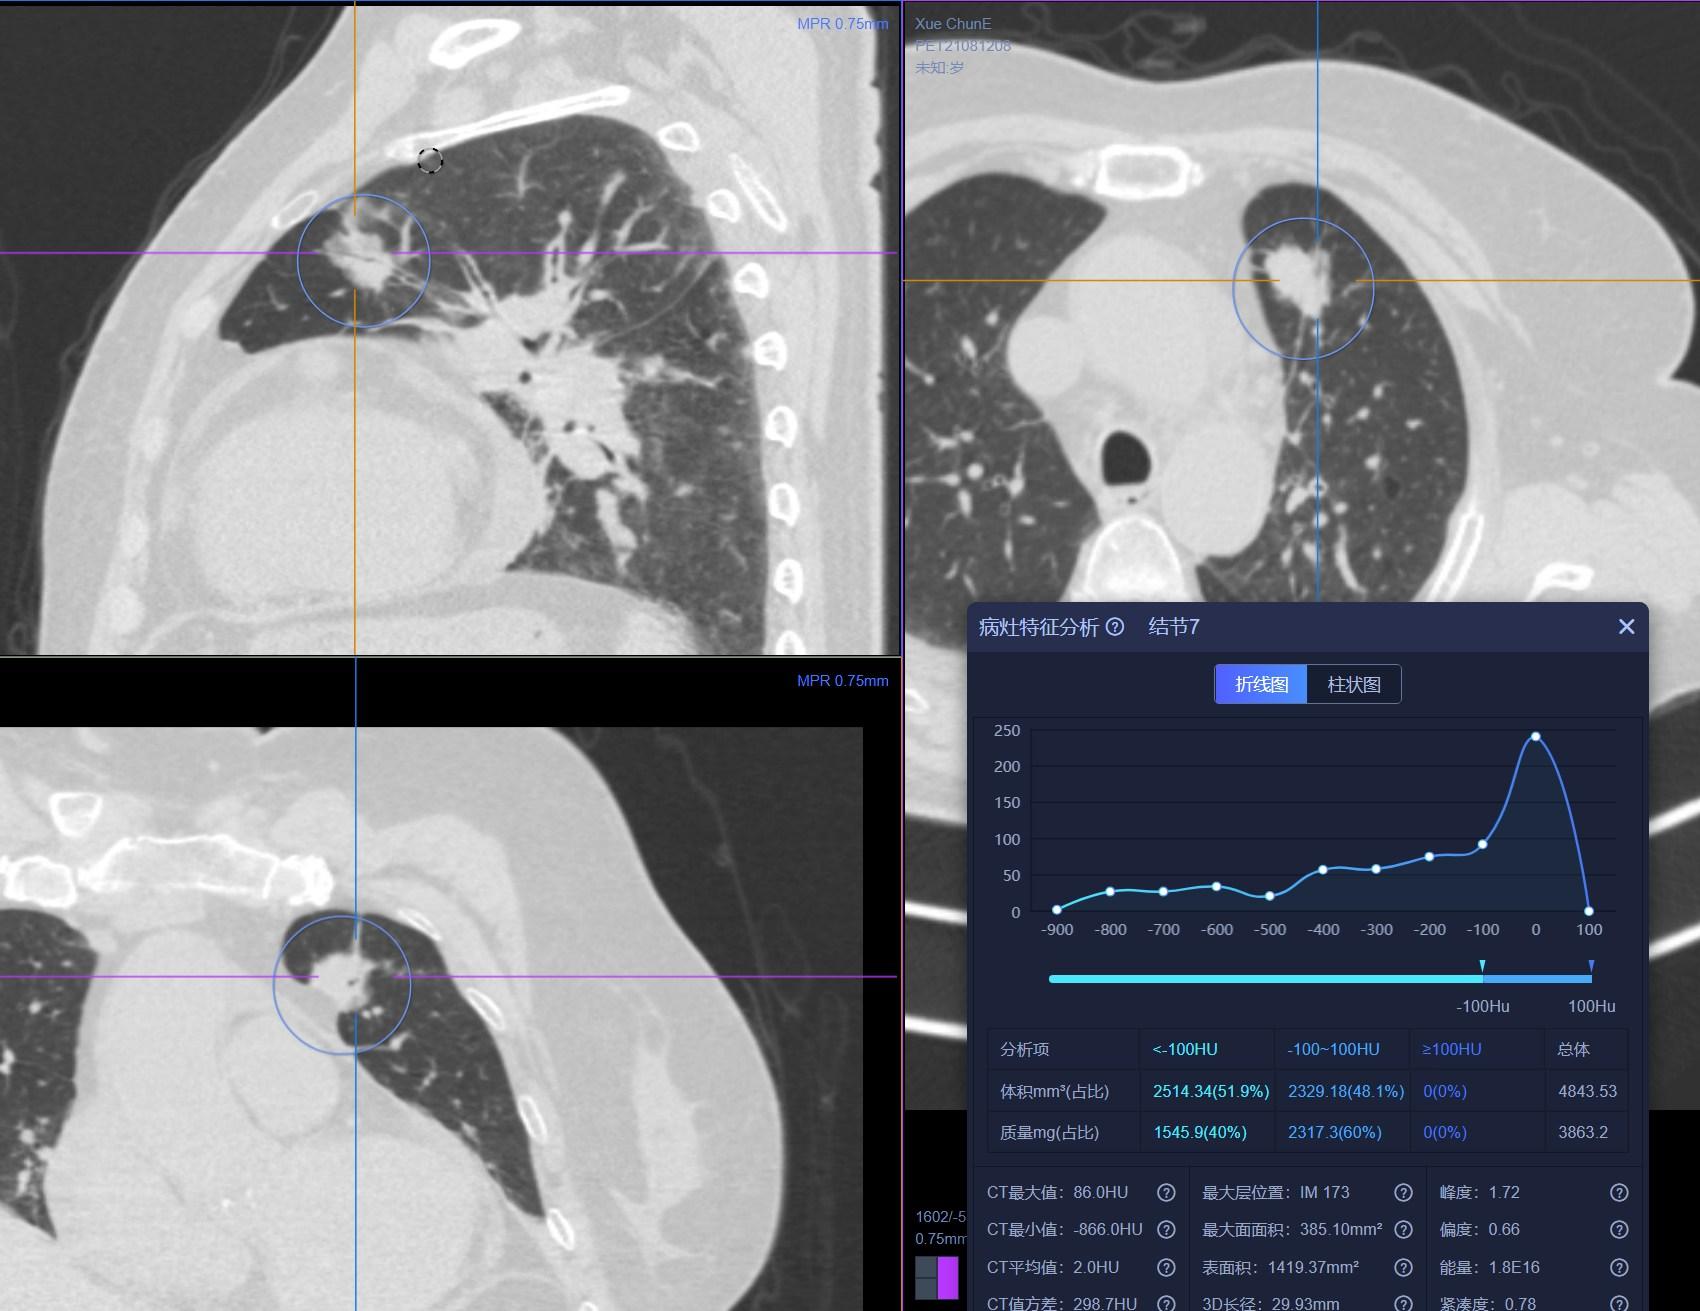

患者1:图1

经常看我科普及所有临床或者影像科医生对这个结节的诊断都没有什么怀疑,病灶大小约2.0cm×1.2cm,实性软组织成分,病灶呈分叶状,周边可见长短不一毛刺,并可见小空洞,相邻胸膜牵拉,全部是恶性征象。单单从CT诊断基本明确。

患者1:图2

另外,薄层CT还提示肺内还发现3个结节,从CT上诊断明确,考虑为纤维增殖灶。